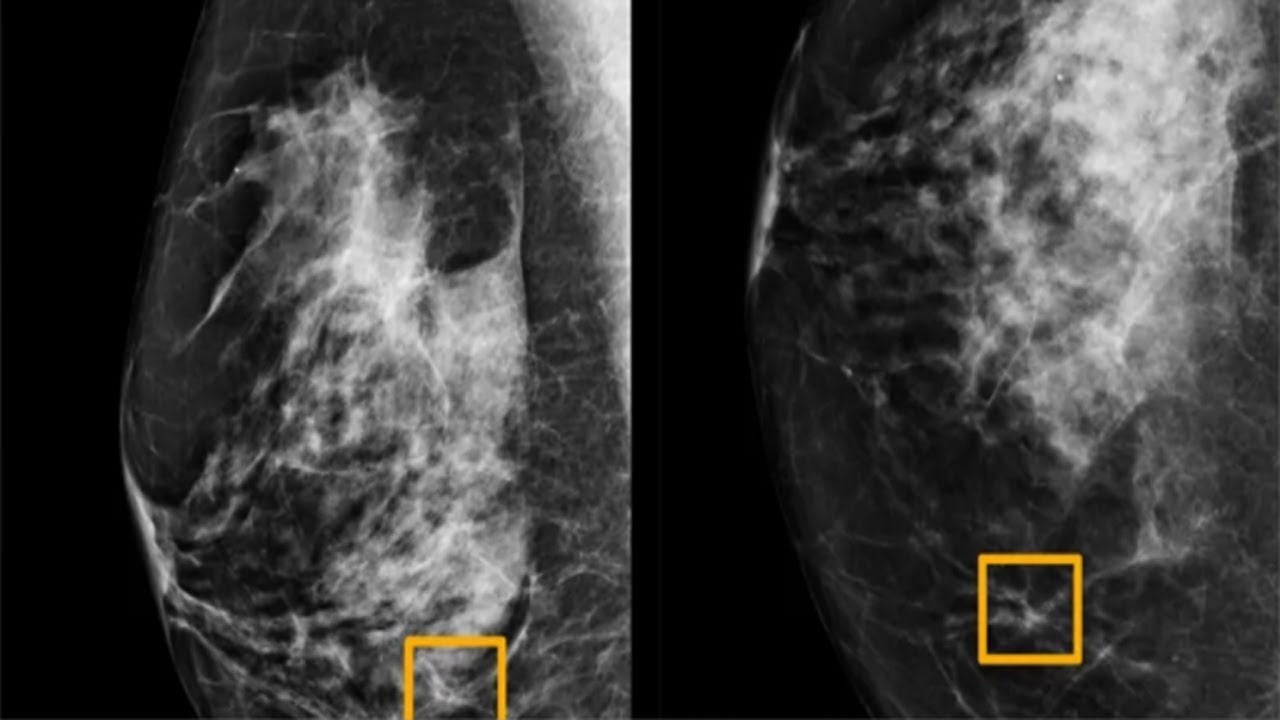

Enter AsymMirai, a groundbreaking AI model designed to predict breast cancer risk up to 5 years in advance. Unlike its predecessors, which function as opaque “black-box” systems, AsymMirai offers a transparent and interpretable approach. It focuses on subtle differences between left and right breast tissue to assess risk, providing a level of accuracy and clarity that could transform breast cancer screening practices.

Artificial Intelligence has long held promise in revolutionizing healthcare, but AsymMirai is setting a new benchmark for innovation. Unlike traditional “black-box” AI systems, AsymMirai employs a transparent methodology that focuses on localized bilateral dissimilarity—subtle differences in breast tissue between the left and right breasts. This novel approach makes the decision-making process not only highly accurate but also interpretable for clinicians.

Here’s how it works: AsymMirai analyzes mammogram images using a convolutional neural network (CNN) to extract key features. It then calculates risk scores based on the differences detected between the two breasts. These risk scores, ranging from 0 to 1, indicate the likelihood of developing breast cancer within 1 to 5 years. The simplicity of this method allows radiologists to understand and trust the model’s reasoning, bridging the gap between technology and clinical practice.